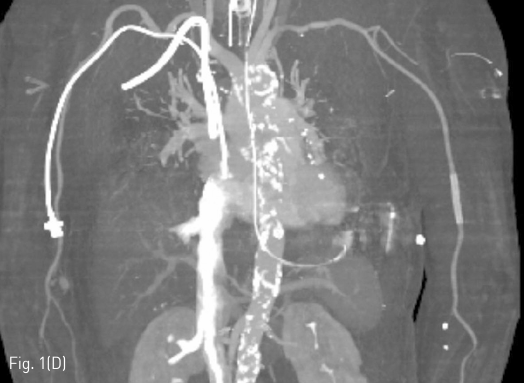

왼쪽 위팔동맥에 혈종 혹은 가성동맥류의 가능성을 염두에 두고 혈관조영술을 시행하기로 하였다. 오른쪽 총대퇴동맥에 7Fr sheath를 삽입한 후, 5F Head Hunter catheter를 이용하여 왼쪽 쇄골하동맥까지 접근한 후, 왼쪽 위팔동맥의 혈관조영술 영상을 얻었다 (Fig. 1A). 천자 부위에서 약 2mm 크기의 목을 갖고 있는 약 60mm x 35mm 크기의 가성동맥류가 관찰되었다. 이를 치료하기 위해 해당 부위를 완전히 덮을 수 있는 스텐트-그라프트를 설치하기로 하였다. 근위부 위팔동맥의 직경은 약 3.5mm였지만, 저혈량 상태가 개선되고 생체징후가 안정화되면 동맥 직경이 커질 것을 감안하여 6mm 스텐트-그라프트를 설치하기로 하였다. 260cm 길이의 stiff guidewire (Glidewire, Terumo, Tokyo, Japan)를 사용하여 6mm-5.5cm Viabahn 스텐트-크라프트 (W. L. Gore & Associates, Flagstaff, Arizona, USA)를 가성동맥류의 목 부위를 충분히 덮도록 설치하였다 (Fib. 1B). 혈관조영술 영상에서 소량의 내강유출이 관찰되어 (Fig. 1C), 5mm Mustang 풍선 카테터 (Boston Scientific, Natick, Massachusetts, USA)을 이용하여 스텐트-그라프트의 근위부와 원위부에 대해 혈관성형술을 시행하였다. 다시 촬영한 혈관 조영술 영상에서 내강유출은 소실되었다.

Fig 1A

(A) Left brachial arteriogram shows a large pseudoaneurysm with a narrow neck at the prior puncture site, with filling of the contrast medium.